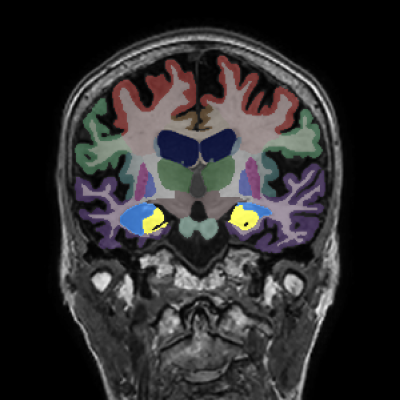

Retrospective brain volumetric analysis in a female patient diagnosed with Alzheimer’s disease at age 77 showed progressive brain atrophy over a 5-year period. The scans demonstrate both hippocampal volume loss and a clear left–right asymmetry.

Retrospective brain volumetric analysis in a female patient diagnosed with Alzheimer’s disease at age 77 showed progressive brain atrophy over a 5-year period. The scans demonstrate temporal cortical atrophy with marked ex-vacuo enlargement of the lateral ventricles.

Hippocampi

Inferior lateral ventricles

Whole brain

Temporal cortex

Hippocampus

Lateral ventricle